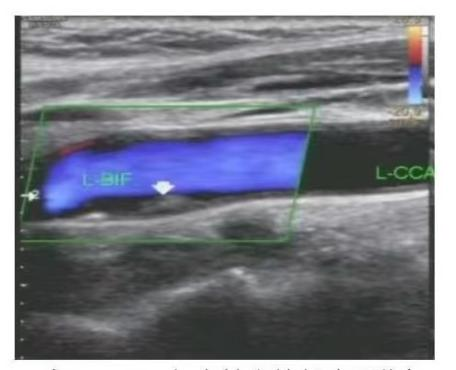

(科室医师为患者检查颈部血管) (颈部血管斑块超声图像)